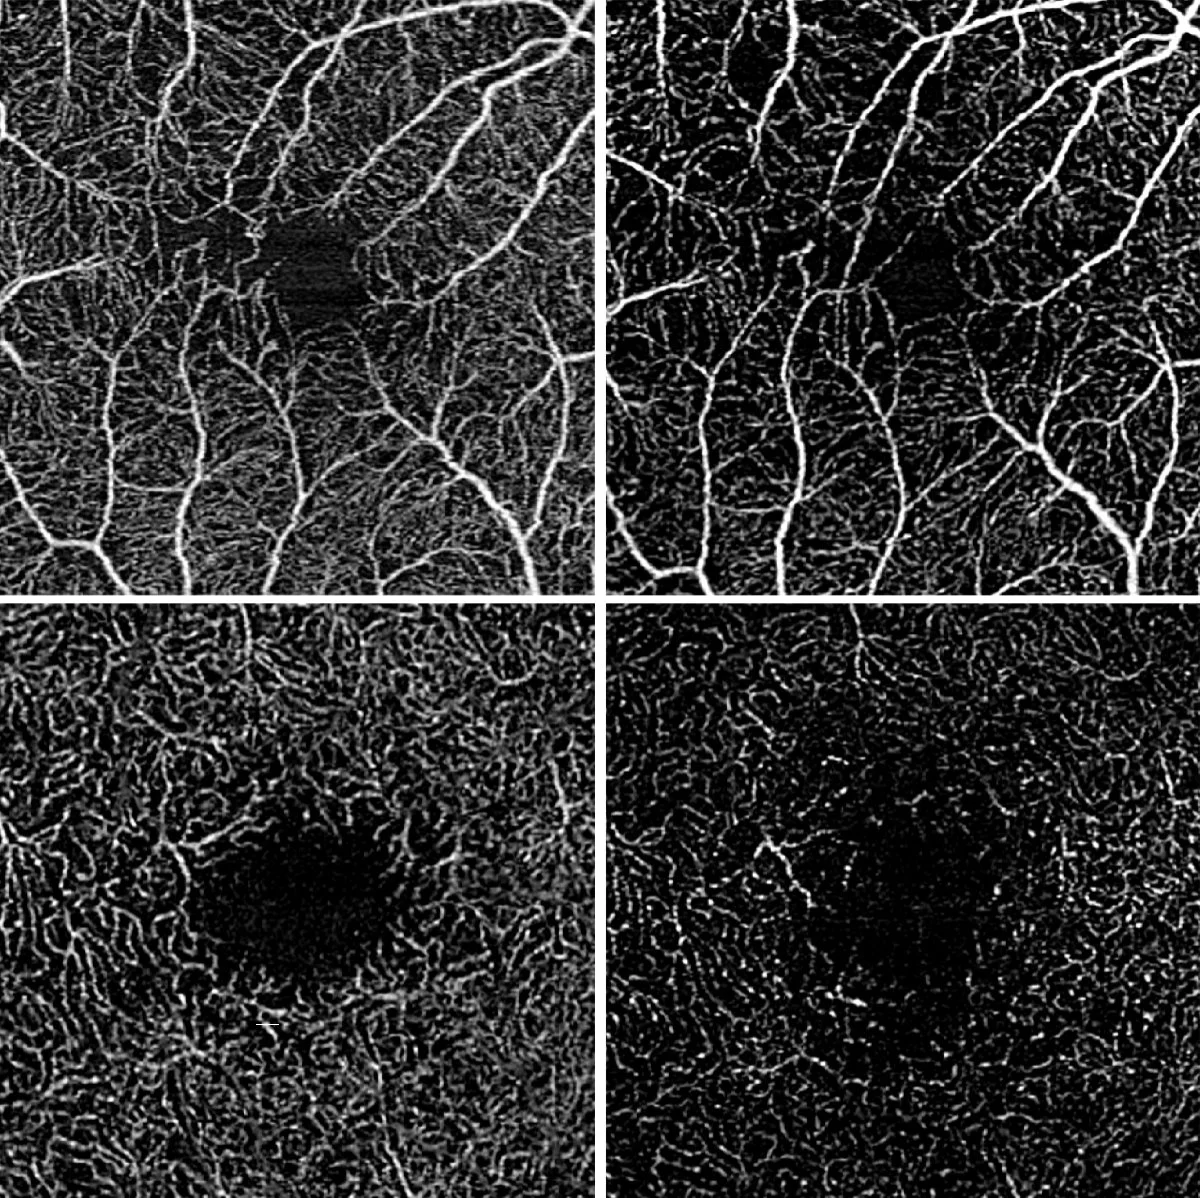

Optical coherence tomography angiography showing ocular vascular perfusion in intermediate uveitis: Home